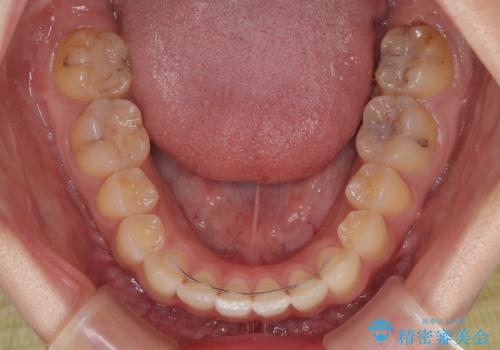

僅か8ヶ月という短期間で、綺麗な歯列に仕上がりました。

- 上下前歯のデコボコを気にして来院された患者様です。